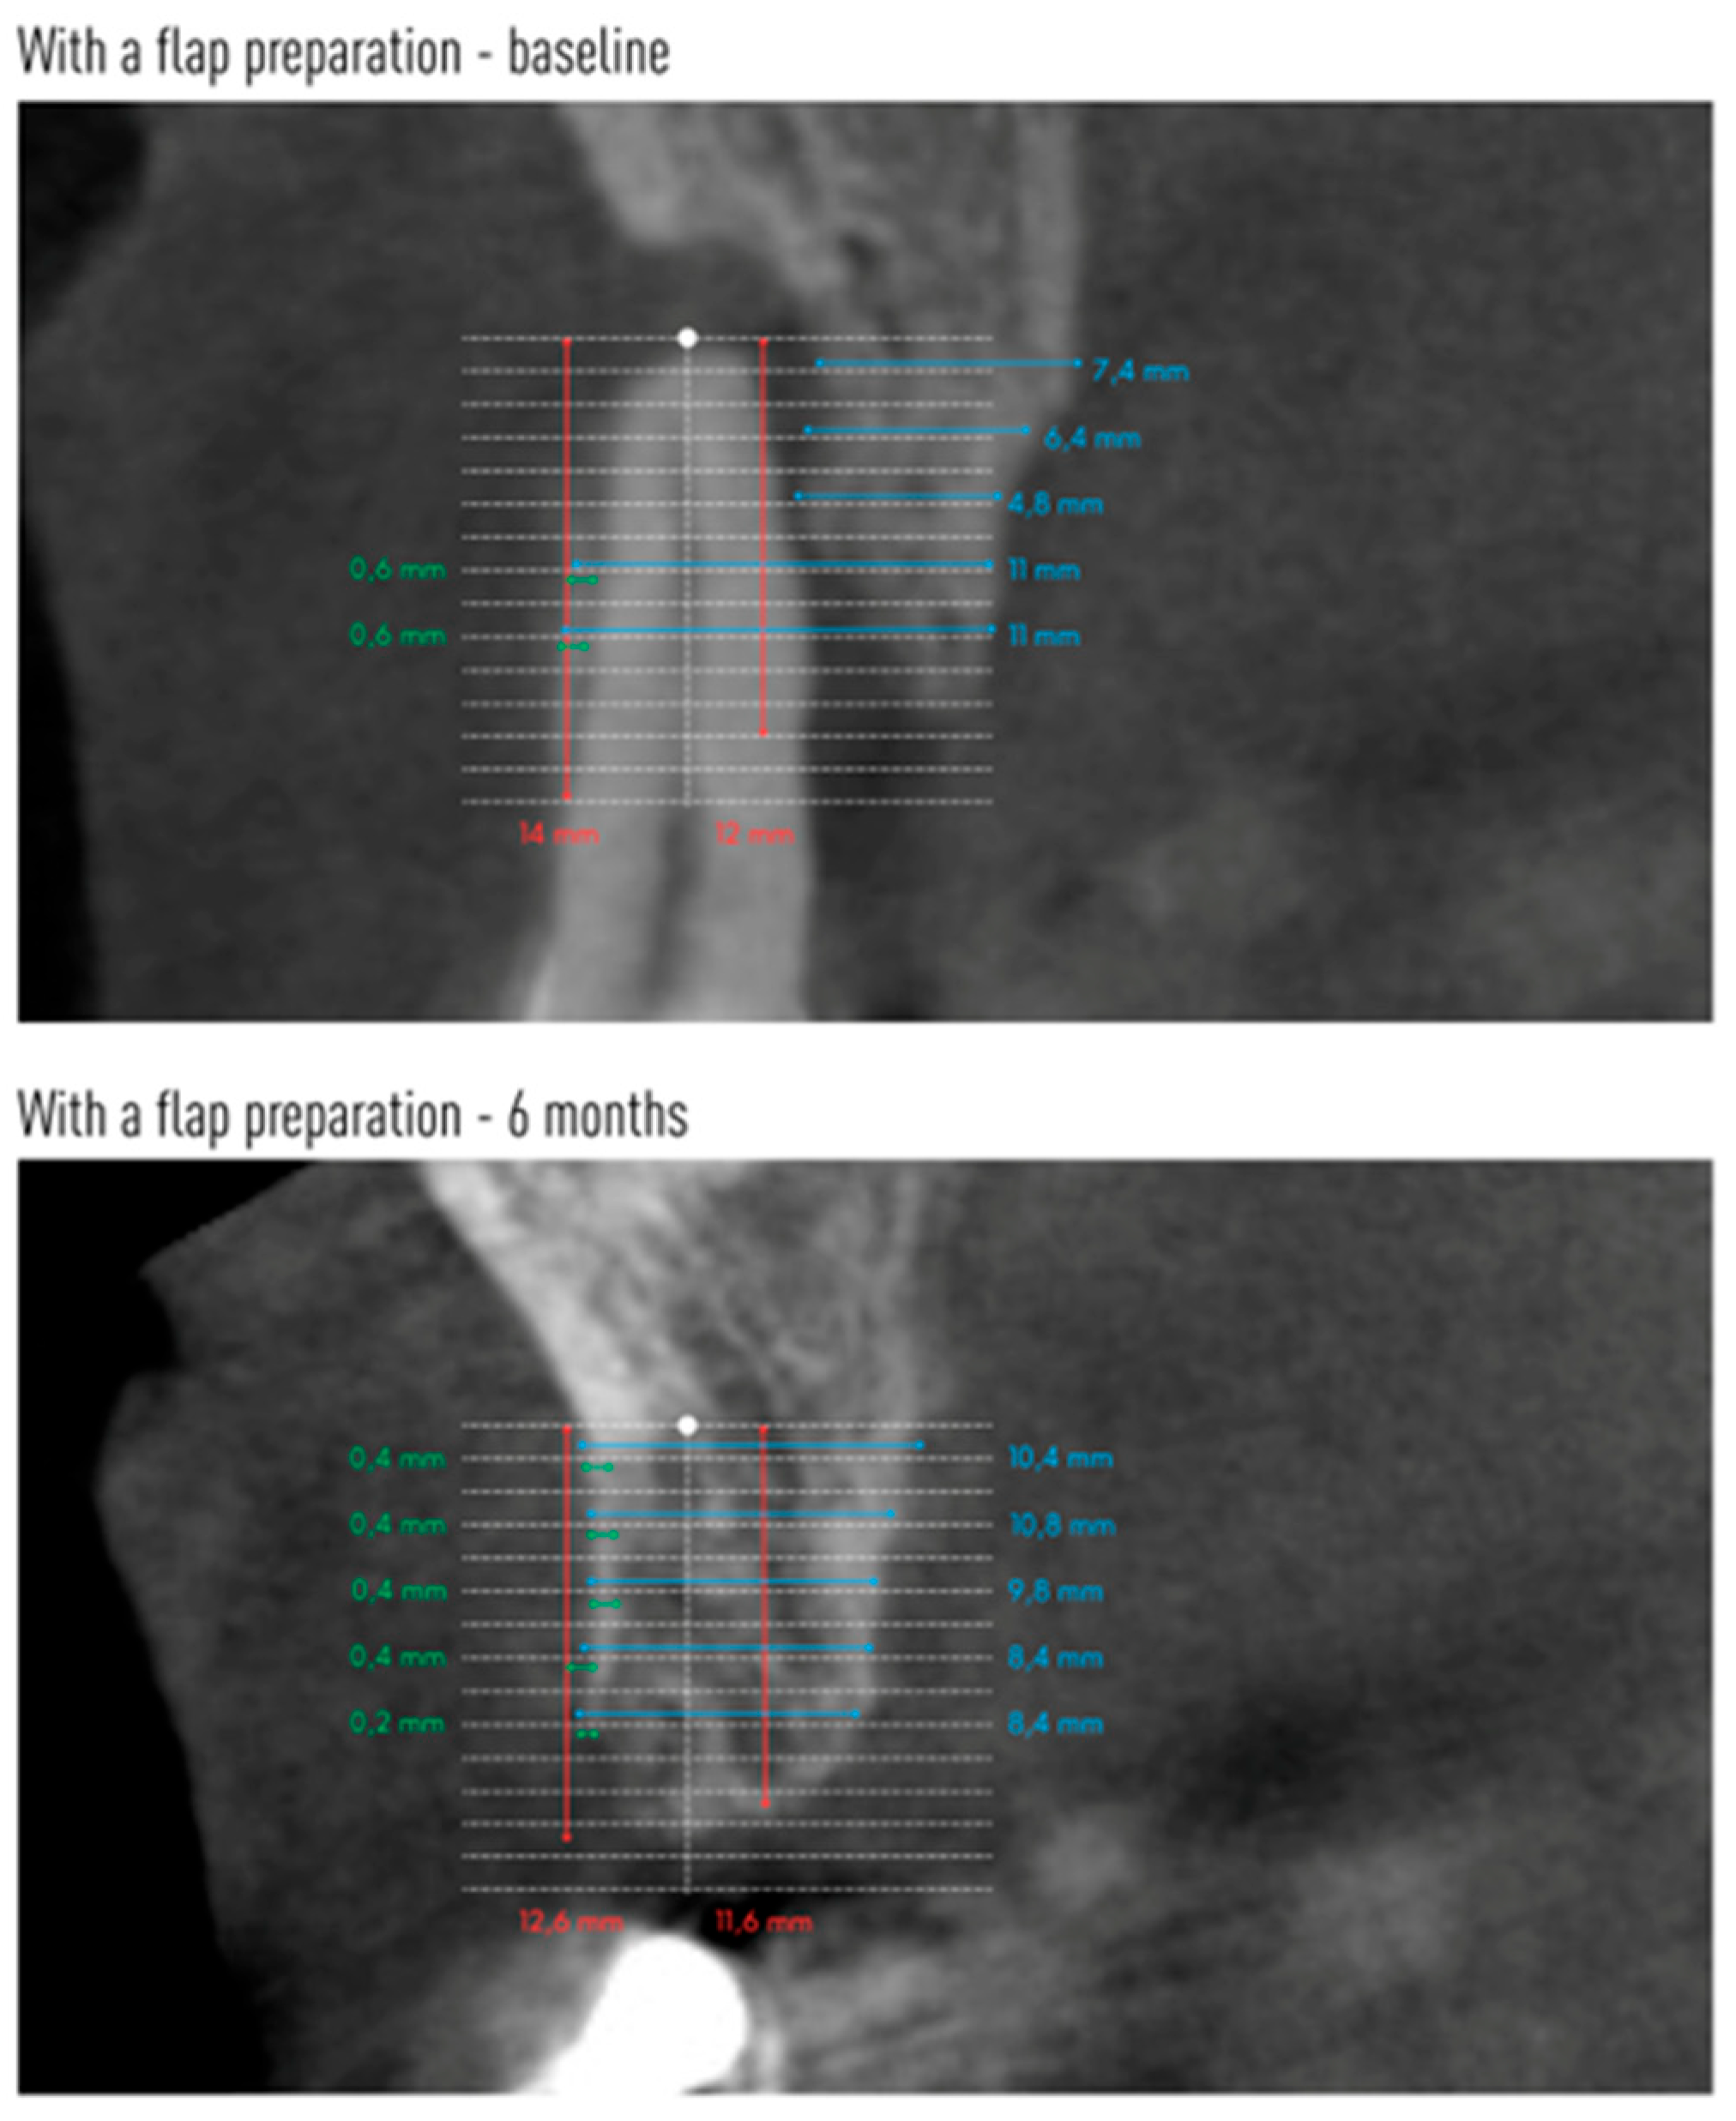

Cone-beam computed tomography (CBCT) was performed before tooth extraction and 6 months after the procedure. Sample scans with measurements marked are shown in Figure 5 (flapless group) and Figure 6 (flap group).

Figure 6.

An example CBCT scans of a patient allocated to flap group with reference lines and measurements made on baseline and after 6 months.

Changes in the mean height of the buccal (BH) and lingual (LH) alveolar bone plates are shown in Table 5. The height of both plates decreased in both groups after 6 months. However, significant radiographic changes in BH and LH were observed only in the group without preparation of the mucoperiosteal flap. In group A, the buccal plate was reduced by an average of 1.08 mm, and the lingual plate by 1.29 mm. There were no statistical differences between the groups.

Changes in the anteroposterior alveolar buccal bone plate thickness (BBP) at 1 mm, 3 mm, 5 mm, 7 mm and 9 mm from the alveolar floor are shown in Table 6. The two groups did not differ with respect to these radiographic parameters before tooth extraction or 6 months after (except for BBP-9 before extraction). However, a decrease in the radiographic width of the vestibular lamina was observed, the greater the farther the measuring point was located from the alveolar floor. In the group with flap preparation, already at a height of 3 mm from the alveolar bottom, as well as 5 mm and 7 mm from the alveolar floor, the reduction in the width of the bone gained statistical significance. At a height of 9 mm from the alveolar floor, the average thickness of BBP9 was only 0.01 mm. In the flapless group, a significant decrease in the thickness of the vestibular compact plate was observed from BBP5 to BBP9.

Table 7 shows the changes in the mean alveolar horizontal width of the entire alveolar process. The radiographic width of the alveolar process was smaller 6 months after tooth extraction at each height in both groups. However, this reduction reached statistical significance only at heights of 5 mm and 7 mm in the flapless group.